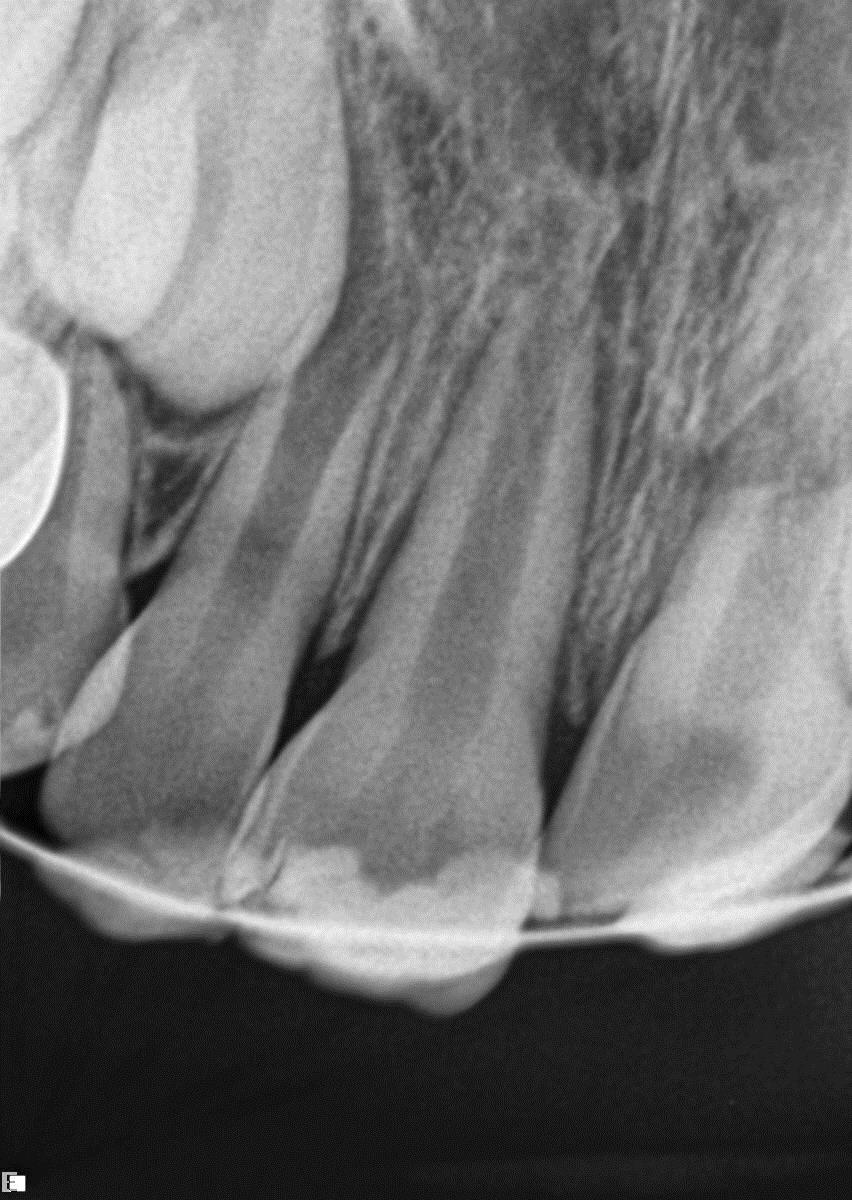

Elly was an active 8-year-old girl; while she and a friend were cartwheeling on Christmas day, she was struck in the mouth by the other girl’s foot. Elly’s upper-right central incisor was avulsed, and the upper left central incisor was palatally luxated (with mid-root horizontal root fracture). Elly’s father placed the avulsed tooth into milk immediately and went directly to her dentist. The dentist replaced the avulsed 11 into its socket and attempted to reposition the 21, but the procedure was unsuccessful. Four days later, Elly presented for assessment.

Fig 2

FIG2